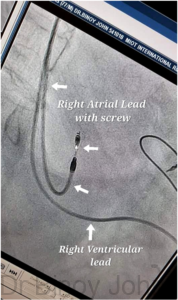

Permanent pacemaker consists of a battery called the pulse generator (PG) and leads or wires (See images). The number of leads placed in the heart may be one (Single chamber pacemaker), where one lead is placed in the right ventricle or two leads (Dual chamber pacemaker), where one lead is placed in the right ventricle and the other is placed in the right atrium. The opposite ends of the leads are connected to the battery which generates the impulses. Some pulse generators can increase the number of beats during activity or exercise called rate-responsive pacemakers.

Then a needle is used to make one puncture (Single chamber pacemaker) or two punctures (Dual Chamber Pacemaker) as required into the axillary vein. Then sheaths are inserted into the veins. Through the sheath first the right ventricular lead is inserted into the RV. (See image)

The lead tip is then screwed on to the RV muscle to prevent displacement. (See image)

Thereafter,if it is a Dual Chamber Pacemaker, the second lead, which is the RA lead is passed via the second sheath into the Right atrium and can be positioned and screwed if required.  (See image)